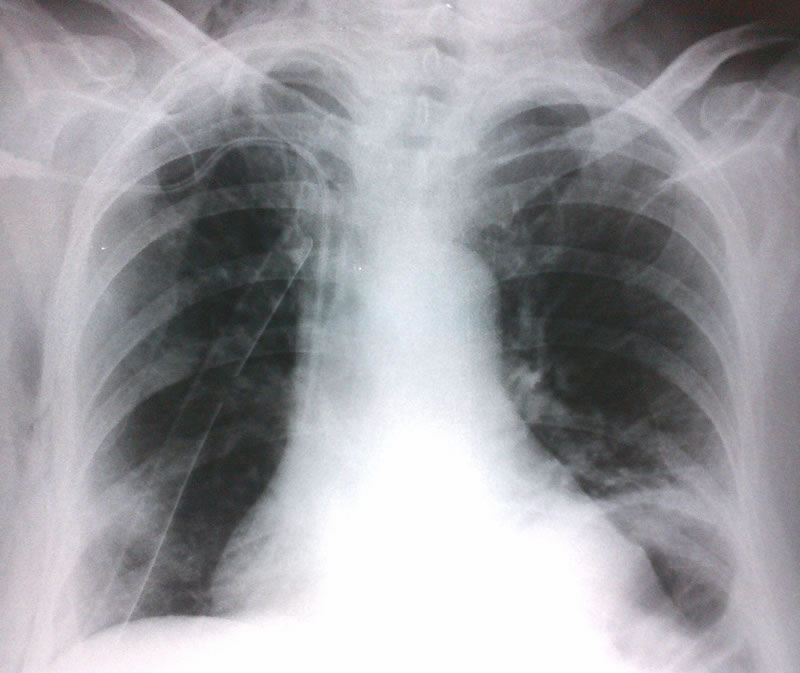

Rx. control

pos - operatorio

Rx. pos - operatoria

inmediata.

a. observe

la expansión pulmonar del lado derecho.

b. El tubo de torax, el cateter de PVC.

c. Dilatacion camara gastrica con contenido aereo, con la consecuente elevacion del diafragma izquierdo.

Rx. pos - operatoria 48 horas.

b. Alguna mejoria de la dilatacion gastrica.

c. En descenso el diafragma izquierdo.